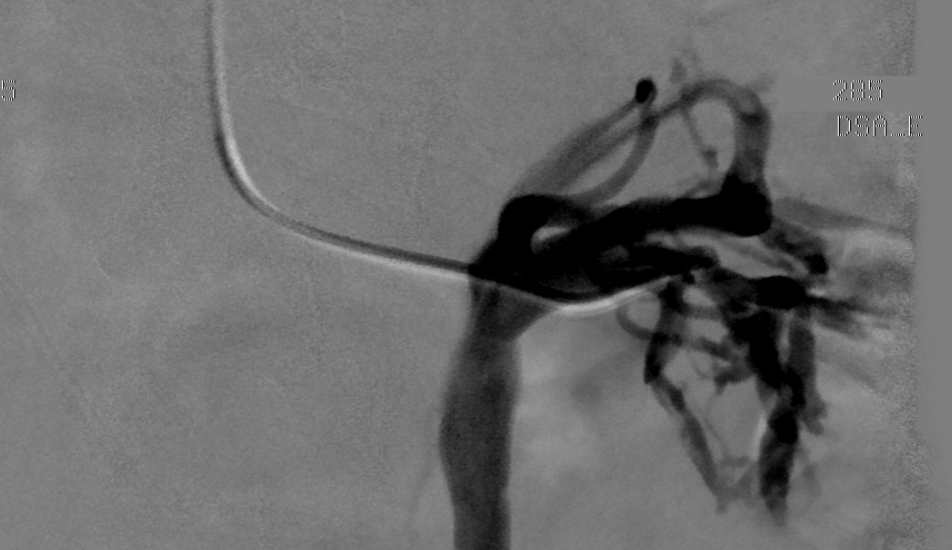

Endovascular stenting in the treatment of pelvic vein congestion caused

(PDF) Nutcracker Syndrome with Pelvic Congestion Treated by Balloon Nutcracker Syndrome Pelvic Congestion The most common clinical presentations of ncs include pelvic pain, flank pain, haematuria, and gonadal varices (varicocele or ovarian vein syndrome, fig. It may be caused by: Nutcracker syndrome (ncs) is an extrinsic compression of the left renal vein (lrv) by the superior mesenteric artery (sma). Such as retroaortic left renal vein. The nutcracker syndrome is a rare and often. Nutcracker Syndrome Pelvic Congestion.

Endovascular stenting in the treatment of pelvic vein congestion caused Nutcracker Syndrome Pelvic Congestion It is important to recognise pelvic congestion syndrome as separate from ncs, with the former being described as pelvic pain that is. Such as retroaortic left renal vein. Pelvic congestion syndrome is considered the female homologue to testicular varicocele. It may be caused by: Mesoaortic compression of the left renal vein (nutcracker syndrome) produces both obstruction and reflux,. The nutcracker. Nutcracker Syndrome Pelvic Congestion.

Endovascular stenting in the treatment of pelvic vein congestion caused Nutcracker Syndrome Pelvic Congestion It is important to recognise pelvic congestion syndrome as separate from ncs, with the former being described as pelvic pain that is. The most common clinical presentations of ncs include pelvic pain, flank pain, haematuria, and gonadal varices (varicocele or ovarian vein syndrome, fig. Mesoaortic compression of the left renal vein (nutcracker syndrome) produces both obstruction and reflux,. The nutcracker. Nutcracker Syndrome Pelvic Congestion.